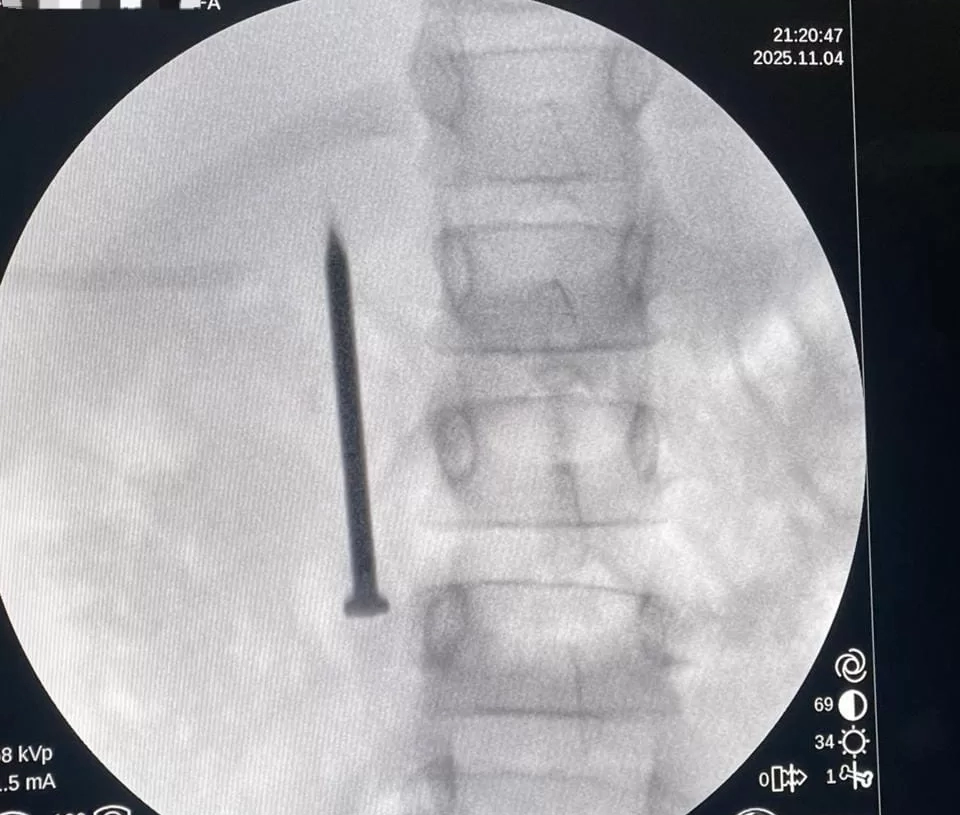

أعلن الدكتور أحمد القاصد، رئيس جامعة المنوفية، عن نجاح فريق طبي متخصص بوحدة مناظير الجهاز الهضمي بمعهد الكبد القومي في إنقاذ حياة طفلة تبلغ من العمر “7 سنوات”، بعد ابتلاعها مسمارًا معدنيًا حادًا يبلغ طوله 4 سنتيمترات.

أوضح رئيس الجامعة،أن الفريق الطبي تمكن من استخراج المسمار الذي وصل إلى الجزء الأول من الأمعاء الدقيقة (الصائم) عبر إجراء منظار طارئ لم يستغرق سوى 20 دقيقة، متجنبًا بذلك خطر الثقب أو النزيف أو الانسداد المعوي الوشيك، و غادرت الطفلة المستشفى بصحة جيدة بعد التدخل الطبي السريع.